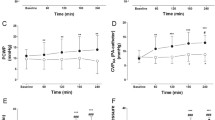

Central nervous system pressures (Table 2)

Unexpectedly, baseline ICP and ISP were above normal levels (mean 18.7 and 13.2 mmHg, respectively). However, increase of IAP to 20 mmHg resulted in statistically significant (p < 0.001) further increases of ICP and ISP, whereas CPP (p = 0.013) and SPP (p = 0.002) decreased significantly under the threshold for ischemia of 60 mmHg [24]. Paradoxically, further increase of IAP to 45 mmHg was followed by a minor increase of ICP and a decrease of ISP, with a concomitant improvement of perfusion pressures above 60 mmHg. After abdominal desufflation all measurements returned to baseline levels.

Cardiovascular system (Figures 1, 2, 3, 4 and 5)

Animals were considered normovolemic due to estimation of the preload status with traditional CVP measurement which was misleading. Calculation of the transmural intracardiac filling pressures revealed that animals were hypovolemic with an associated tachycardia (Figure 1). Heart rate initially decreased in phase T2, but was increased in the two subsequent phases, with a parallel increase in MAP and a decrease of APP (Figure 2). Cardiac output and cardiac index were decreased in phase T3 and restored to baseline levels after abdominal desufflation (Figure 3). Systemic and pulmonary vascular resistances increased significantly with IAH and decreased after abdominal desufflation (Figure 4). IVCP reflected accurately the changes in IAP (Figure 5).